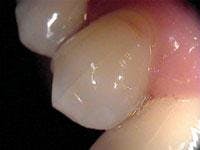

Treatment of the tooth depends on the degree of pulpal involvement and the extent of the crack. Those cracks, which are visualized but remain asymptomatic and clinical testing (such as percussion, palpation, mobility, probing, and thermal testing) is within normal limits, should be treated with a crown or some other form of complete cuspal coverage (see Figure 3). This is to prevent further propagation of the crack and the onset of symptoms. However, if a patient exhibits more extensive symptoms from the start, including increased sensitivity to thermal provocation and percussion/biting, root canal therapy should be performed prior to placement of a crown. These are considered incomplete vertical root fractures. A study by Kahler8 showed that all symptomatic cracks in teeth appeared to extend right through the dentin to the dentino-enamel junction and were extensively contaminated by bacteria. Hence, root canal therapy and crowning for all symptomatic cracks are recommended.